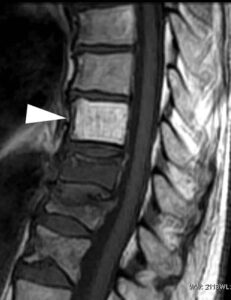

Catanzaro, 03 maggio 2010 – Le fratture vertebrali dolorose da compressione rappresentano uno dei maggiori fattori invalidanti in alcune patologie ematologiche e oncologiche, come il mieloma multiplo e le metastasi vertebrali dovute a neoplasia del polmone, della mammella, della prostata, del colon, dell’esofago, dell’utero e dell’osso stesso.

Le conseguenze di queste fratture sono molteplici: oltre al dolore vertebrale e la disabilità, i pazienti soffrono anche di ridotta mobilità e dell’insorgenza di deformità spinali come cifosi e scoliosi. Il trattamento finora utilizzato prevedeva l’immobilizzazione forzata del paziente con impiego di busto, radioterapia, assunzione di notevoli dosi di farmaci antidolorifici ed eventuali interventi di stabilizzazione vertebrale estremamente invasivi.

“Il miglior procedimento per trattare fratture vertebrali di questo tipo è la stabilizzazione meccanica, che oggi può essere ottenuta con l’impiego di una metodologia, detta cifoplastica con palloncino, che consiste nell’iniezione a bassa pressione di cemento osseo in una cavità creata nei corpi vertebrali crollati da una dilatazione di un palloncino introdotto bilateralmente per via percutanea – dichiara il Prof. Angelo Lavano, responsabile dell’Unità Operativa di Neurochirurgia del Centro Oncologico Fondazione “Tommaso Campanella” del Policlinico Universitario di Germaneto di Catanzaro – Questa tecnica è stata ideata per ridurre prima e stabilizzare poi la frattura in modo controllato, correggere le deformità della colonna vertebrale, prevenire l’insorgere di nuove fratture e soprattutto alleviare il dolore in modo rapido e prolungato e migliorare la qualità della vita del paziente.“

“Dei 49 pazienti seguiti, 38 erano affetti da metastasi vertebrali, e in 11 la diagnosi principale era di mieloma multiplo. I risultati clinici sono stati determinati confrontando i dati pre e postoperatori secondo scale di misurazione del dolore – scala VAS – e della qualità della vita – spiega il Prof. Lavano – Dopo l’intervento è stato riscontrato un notevole e duraturo miglioramento della sintomatologia dolorosa associato ad un miglioramento delle attività di vita quotidiane nel 89% dei pazienti; in alcuni casi si è ottenuto anche un significativo aumento dell’altezza del corpo vertebrale da un punto di vista radiologico, con conseguente parziale correzione della deformità della colonna. Inoltre, a seguito dell’intervento, non sono state registrate complicanze cliniche rilevanti e quasi tutti i pazienti – 45 su 49- sono stati dimessi in 2° giornata. Dall’analisi dei risultati ottenuti si può concludere che la cifoplastica con palloncino rappresenta un semplice e valido trattamento per le fratture vertebrali su base onco-ematologica in termini di risoluzione della sintomatologia dolorosa, di miglioramento della qualità della vita e di stabile e duratura riduzione delle deformità.”